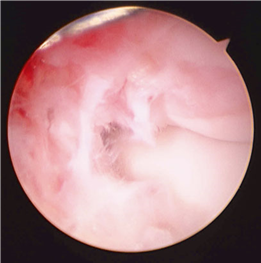

The sesamoid complex, embedded within the flexor hallucis brevis (FHB) tendons, acts as a fulcrum to increase the mechanical advantage of the intrinsic flexors. The tibial (medial) and fibular (lateral) sesamoids articulate with the plantar facets of the first metatarsal head, separated by the crista. In severe hallux valgus, the metatarsal head pronates and drifts medially off the sesamoid apparatus, leading to erosion of the crista and intractable pain. Surgical realignment must restore this delicate sesamoid-metatarsal relationship to ensure long-term success and prevent recurrence.

First MTP Arthrodesis

In cases of end-stage hallux rigidus, first MTP arthrodesis yields excellent, predictable outcomes. A dorsal longitudinal incision is made just medial to the EHL tendon. The joint is exposed, and aggressive cheilectomy is performed to remove all dorsal, medial, and lateral osteophytes. The remaining articular cartilage on the metatarsal head and the base of the proximal phalanx is resected using cup-and-cone reamers, which allow for infinite adjustment of the joint position prior to fixation.